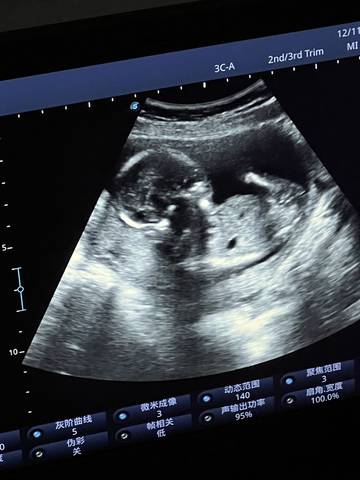

各位宝妈们,麻烦帮我看一下这是男孩还是女孩,好奇心满满????

journal_insert_pic_1678140510journal_insert_pic_1678140553

你好亲爱的,通过这个来判断男孩女孩是不太准确的哈。那么这个男孩女孩都是我们最爱的宝贝哈,我们要给他同等的关爱和呵护,也祝你可以如愿以偿,心想事成,祝你好运。

您好,看着这个图片有点感觉是个男孩子来的,不过建议你到时候有宝宝的图片的时候再发出来看一下

你好,根据你发的检查报告是看不出来宝宝的性别的,建议宝妈还是安心养胎,只要宝宝健健康康的就好

通过这些是看不出来的,而且也不准确,在怀孕期间的话你也不要想太多,我觉得只要宝宝发育好的话就可以,男孩女孩都一样的。